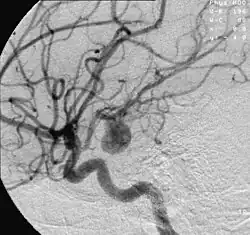

A caracterização de um aneurisma é realizada por um exame de imagem, tomografia computadorizada, ressonância magnética ou angiografia cerebral, que permitem ao médico identificar a área do cérebro afetada.

O exame padrão ouro para detecção de aneurisma cerebral não é a tomografia ou a ressonância magnética, e sim o cateterismo cerebral de 4 vasos, denominado angiografia cerebral. Entretanto, não costuma ser o primeiro exame realizado.

Tratamento por Via Endovascular

O tratamento por embolização dos aneurismas cerebrais começa com a inserção de um cateter (pequeno tubo plástico) na raiz da coxa, na artéria femoral na perna do paciente e navegação dele pelos vasos arteriais, passando pela pelva, abdômen, tórax, pescoço e base do crânio até o aneurisma. Através desta viagem pelo corpo, retificadas pelo cateter, pequenas molas ou espirais de platina são inseridas aos poucos dentro do aneurisma. O processo é assistido por meio de imagens radiológicas, visualizadas em um monitor de vídeo. Ao serem destacadas do cateter são desdobradas dentro da luz no aneurisma, ocupando aos poucos o interior, interferindo no fluxo de sangue para o interior do aneurisma, causando coagulação da luz, redução da pressão interna provocada pela pressão sanguínea e prevenindo sua ruptura. As molas são feitas de platina para que eles possam ser visíveis pelo raio x e bastante flexíveis para conformar-se com a forma de aneurisma e tentar evitar que ele se rompa. Um grande número de pacientes no mundo inteiro já foram tratados com molas de platina destacáveis. As micro-molas mais utilizadas para a embolização do aneurisma são as molas destacáveis de Guglielmi.

Os médicos, preferencialmente neurorradiologistas experientes em intervenções por angiografia encefálica, usam a tecnologia de raios-X em tempo real, chamada visualização fluoroscópica (radioscopia), para visualizar o interior dos vasos sanguíneos. As características externas do aneurisma apenas podem ser visibilizadas pela cirurgia aberta.